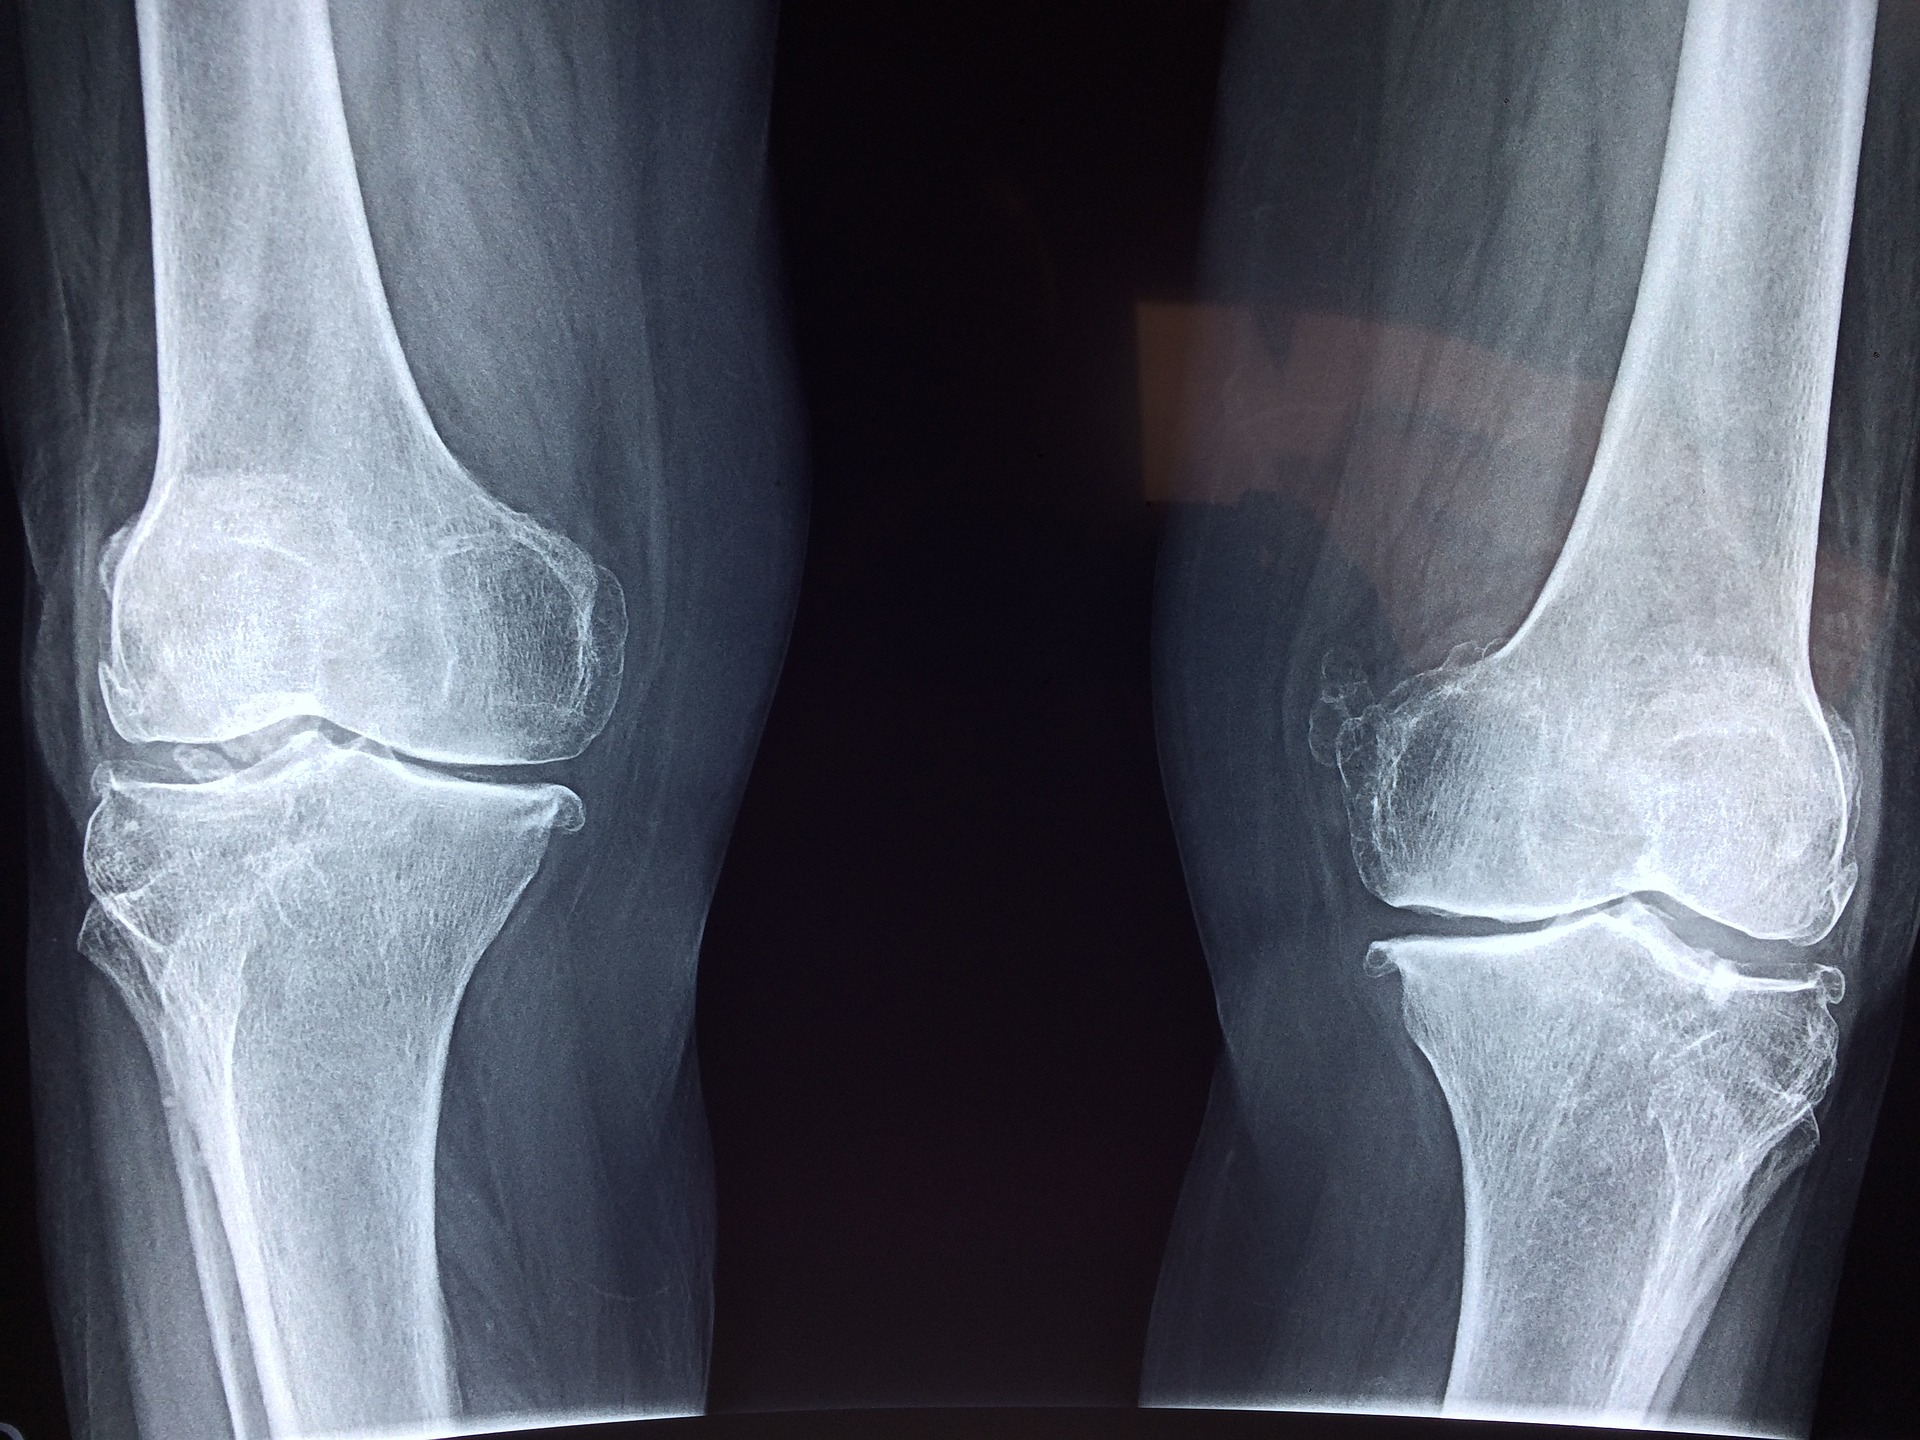

실제 관절은 이보다 훨씬 더 복잡합니다. 예를 들어 무릎관절의 특징을 보면 첫째, 무릎관절을 실제 3개의 독립적인 관절로 이루어져 있고 특별히 발달된 힘줄과 인대, 연골이 있습니다. 윤활관절처럼 무릎뼈의 끝부분은 희고 부드러운 관절의 연골로 덮여 있습니다. 둘째, 무릎에는 특이하게도 뼈 사이에 충격을 습수하는 반달 모양 연골이 한 쌍 존재합니다. 찢어져서 때로 치료나 대치가 필요한 부위가 바로 반달 모양 연골입니다. 관절은 광범위한 움직임을 수행하는 복잡한 구조를 지니고 있으며 고장 날 가능성도 그만큼 크다고 볼 수 있습니다.

관절은 쉽게 삐거나 부러져 탈구되거나 골절됩니다. 탈구된 관절은 대개 아주 아프고 이상하게 보이며, 정상적으로 움직일 수 없어 아픈 팔다리를 늘어뜨리게 됩니다. 모든 탈구는 응급실에서 신속히 치료해야 하는데 뼈를 제자리에 빨리 돌려놓을수록 결과가 좋기 때문입니다.